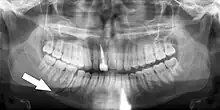

Panoramic radiograph of a simple mandible fracture of the right mandibular body, minimally displaced. Note that the teeth to the left of the fracture do not touch